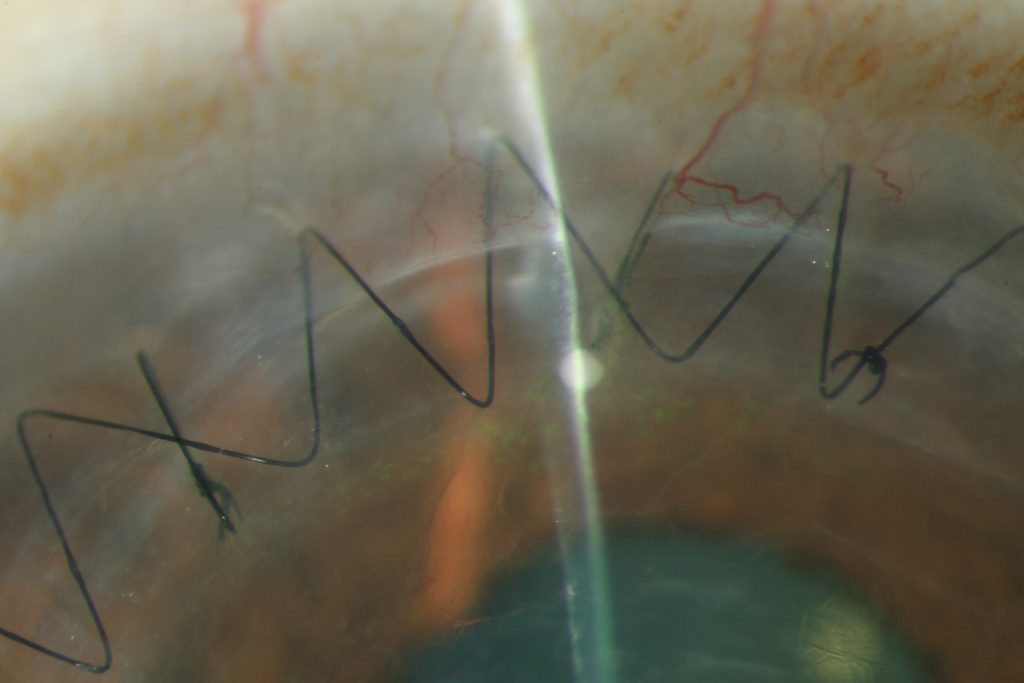

The cornea is the clear, transparent tissue at the front-most part of the eye, functioning as the window to the eye. The cornea, together with the natural lens inside the eye, refract (or bend) light coming from the outside world and refocus them onto the retina for a clear image. Therefore, any disease or process that interferes with the cornea may interfere with this light-bending process and blur one’s vision.

Corneal diseases result from many causes ranging from infectious, inflammatory, structural, and traumatic origins. A few examples are illustrated below. If you have a corneal disease that adversely affects your sight, please see our fellowship-trained cornea specialist for a medical consultation. Some corneal diseases may cause irreversible vision loss if not treated in a timely manner.